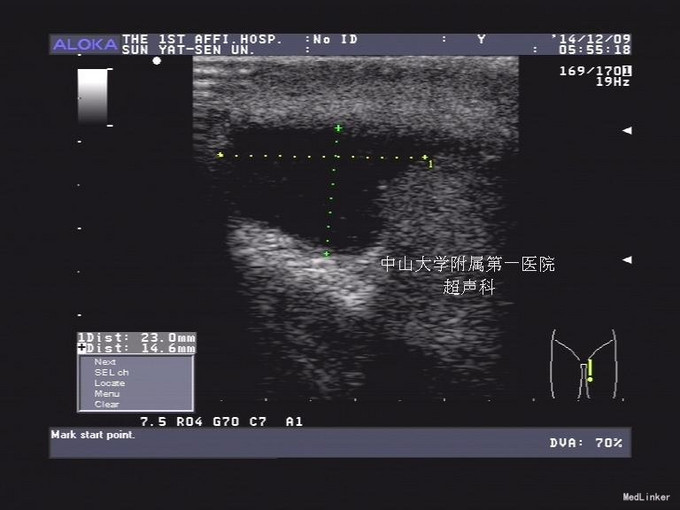

查体:左侧阴囊稍肿大,睾丸肿大,质偏硬,触痛,抬高阴囊可缓解 辅助检查:超声提示睾丸扭转 左侧精索水肿迂曲,考虑睾丸扭转。 左侧睾丸少量鞘膜积液。 右侧睾丸未见明显异常。双侧附睾未见病变。

左侧睾丸扭转 左侧睾丸扭转复位固定术 1、麻醉成功后取平卧位,常规会阴区术野消毒铺巾。 2、取阴囊中线纵行切口,长约5cm,逐层切开皮肤,肉膜层,打开左侧睾丸鞘膜,见左侧睾丸,附睾明显肿大、淤血,呈暗褐色,精索顺时针扭转360°。睾丸附睾系带较长。逆时针复位睾丸及精索,温水热敷睾丸,观察睾丸、附睾颜色稍转粉红色,考虑保留睾丸:切除多余睾丸鞘膜将睾丸正位还纳阴囊内,1#丝线将三点缝合睾丸固定于肉膜层。 3、打开右侧睾丸鞘膜,见右侧睾丸,附睾未见异常,翻转睾丸鞘膜,1#丝线三点缝合睾丸正位固定于肉膜层,双侧阴囊放置橡皮引流片。5-0可吸收缝线缝合肉膜层及皮肤。无菌敷料包扎切口。